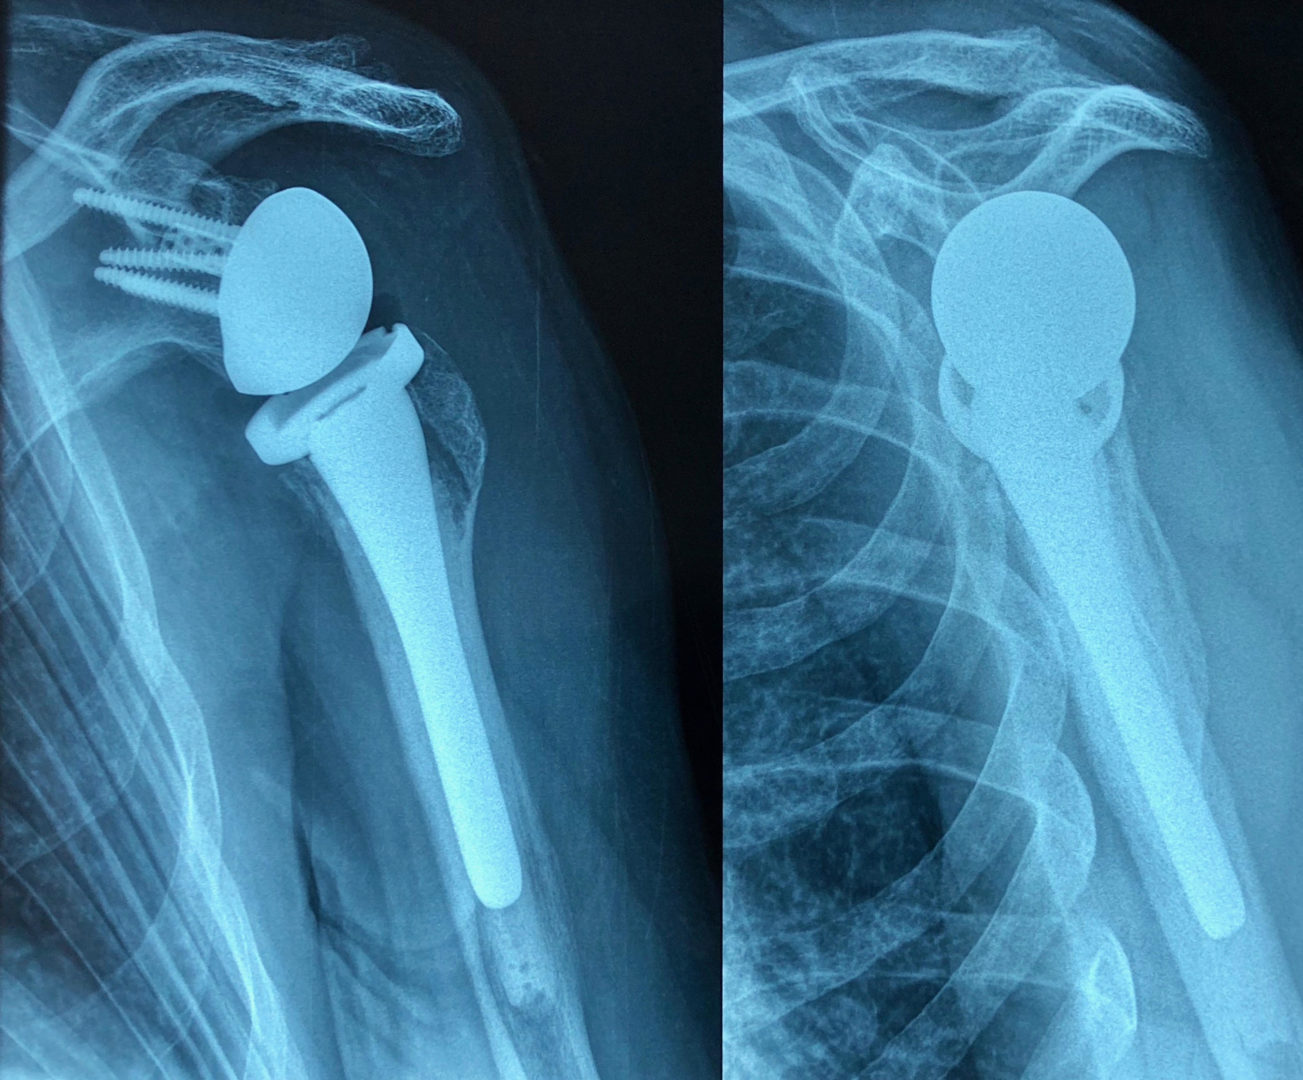

Dans ce propos, nous allons tâcher d’éclairer le lecteur sur la nature des implants utilisés en chirurgie orthopédique pour réaliser les prothèses articulaires (hanche, genou, épaule, coude, cheville, articulations des doigts…). Les termes prothèses articulaires et arthroplasties sont interchangeables même si une nuance puriste peut exister. Le but d’une prothèse articulaire est de remplacer une articulation détruite suite à l’usure liée à l’âge, une infection, une tumeur ou un traumatisme par des implants inertes destinés à restaurer la fonction. On précisera cependant qu’il ne s’agit pas ici de prothèses – appareillages destinées à remplacer un membre amputé.

Actuellement, l’amélioration de la qualité des matériaux ainsi que de leur usinage, surtout le polissage de la surface de friction, ont permis de porter la durée de vie des prothèses au-delà de 30 ans. Trois catégories de matériaux sont actuellement utilisées. Il s’agit des alliages métalliques, des céramiques et du polyéthylène de haute densité. Des essais d’implants en carbone sont en cours.

Les alliages métalliques sont essentiellement en chrome – cobalt et en titane. Les céramiques sont des matériaux non métalliques et non organiques obtenus par l’effet de fortes températures sur de l’alumine ou du zircon. Le polyéthylène est un matériau plastique issu de l’industrie pétrochimique. Il sert à constituer la surface de friction des implants. L’introduction du ciment acrylique dans la fixation des implants à l’os date du début des années 60. Depuis le milieu des années 80, le concept de prothèse sans ciment est apparu. Le principe consiste à recouvrir la surface de contact des implants avec l’os d’un revêtement dit ostéo-conducteur. Il s’agit de l’hydroxyapatite, un composant minéral naturel de l’os que l’on produit artificiellement. Au contact de la prothèse, l’os du voisinage identifie cet hydroxyapatite comme un de ses propres constituants et le colonise. La prothèse devient ainsi intégrée à l’os. On parle alors de stabilité secondaire. Naturellement, en attendant cette repousse d’os sur le revêtement d’hydroxyapatite, la stabilité primaire est assurée par l’impaction en force de la prothèse dans l’os et éventuellement fixée par des vis complémentaires. Les couples de friction (surface de frottement des implants) sont de plusieurs sortes : métal – PE, céramique – PE, céramique – céramique. Le couple métal – métal dit de gros diamètre a été utilisé au moins durant trois périodes depuis le 20ème siècle dont la dernière au-début des années 2000 avant d’être à nouveau abandonné pour cause de relargage excessif de particules de métal dans l’organisme.